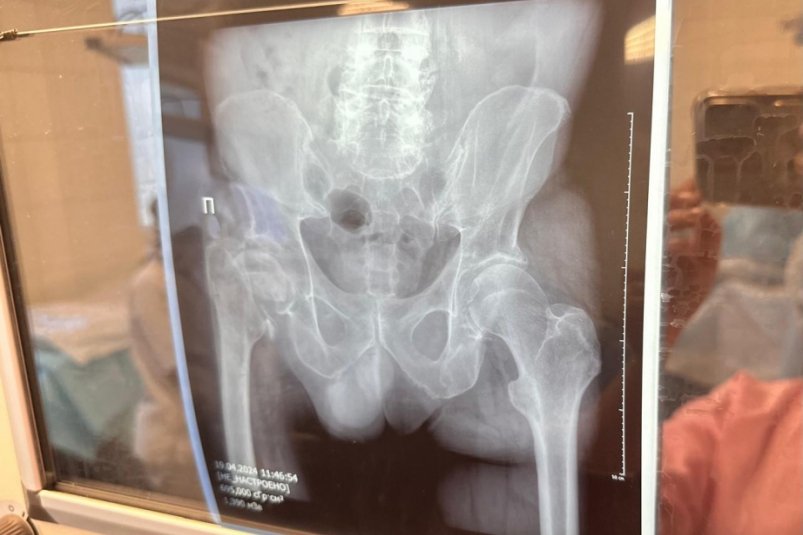

Краевая клиническая больница имени профессора Владимирцева увеличивает количество операций по эндопротезированию тазобедренных и коленных суставов, сообщает ИА AmurMedia со ссылкой на информацию пресс-службы правительства Хабаровского края. Высокотехнологичную помощь при наличии показаний пациенты получают бесплатно по полису ОМС.

Для сравнения — количество операций по эндопротезированию тазобедренных суставов в больнице: в 2019 году — 250, в 2023 году — 675. В первом квартале 2024 года помощь оказали уже 166 пациентам, а план на год — свыше 1000 операций по эндопротезированию.

На этот год всего в больнице запланировано провести свыше 1000 операций по эндопротезированию, больше половины связаны с заменой тазобедренных суставов.